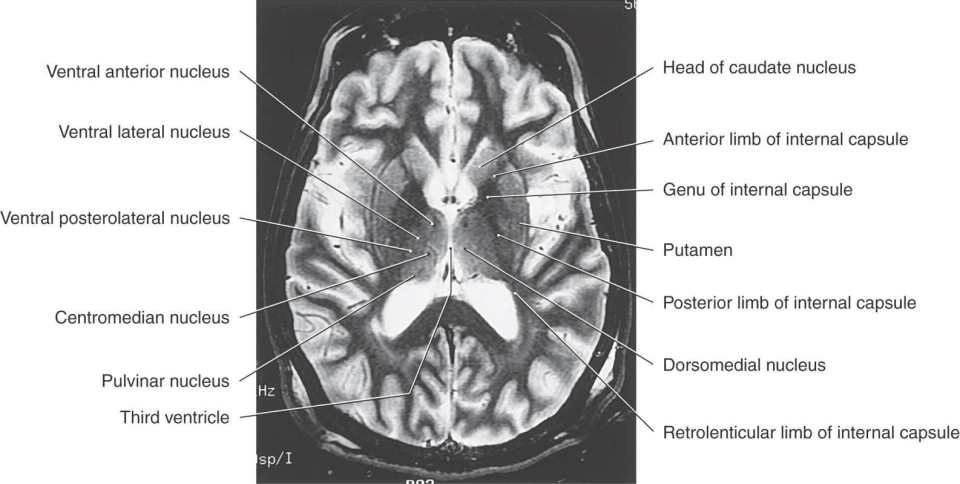

Figure 15-9. T2-weighted magnetic resonance image of the cerebral hemisphere in the axial plane. Emphasis in labeling is on diencephalic structures. Compare with Figure 15-12.

An internal medullary lamina, also consisting of myelinated fibers, extends into the substance of the thalamus, where it forms partitions or boundaries that divide the thalamus into its principal cell groups (Figs. 15-9 and 15-10): the anterior, medial, lateral, and intralaminar nuclear groups. The last cell group is located in the portion of the internal medullary lamina that separates the lateral and medial nuclear groups. In addition, there are midline thalamic nuclei located just superior to the hypothalamic sulcus.

This large collection of thalamic neurons is grouped into dorsal and ventral tiers. The relatively small group of dorsal tier nuclei includes the lateral dorsal and lateral posterior nuclei along with the much larger pulvinar nucleus (pulvinar) (Figs. 15-7B-D, 15-8D, 15-9, and 15-10). The connections of the lateral dorsal and lateral posterior nuclei are formed with the cingulate gyrus and parietal lobe, respectively (Fig. 15-10). The large pulvinar nucleus consists of anterior, medial, lateral, and inferior subdivisions. The inferior division receives input from the superior colliculus and projects to the visual association cortex. Other portions of the pulvinar project to areas of the temporal, parietal, and frontal lobes that are especially concerned with visual function and eye movements (Fig. 15-11).

The large ventral tier of the lateral group consists of three separate nuclei (Figs. 15-7, 15-8B, C, and 15-9). The ventral anterior nucleus (VA) and the slightly more caudal ventral lateral nucleus (VL) are important motor-related nuclei; the ventral posterior nucleus, consisting of ventral posterolateral (VPL) and ventral posteromedial (VPM) nuclei, convey somatosensory information to the cerebral cortex.